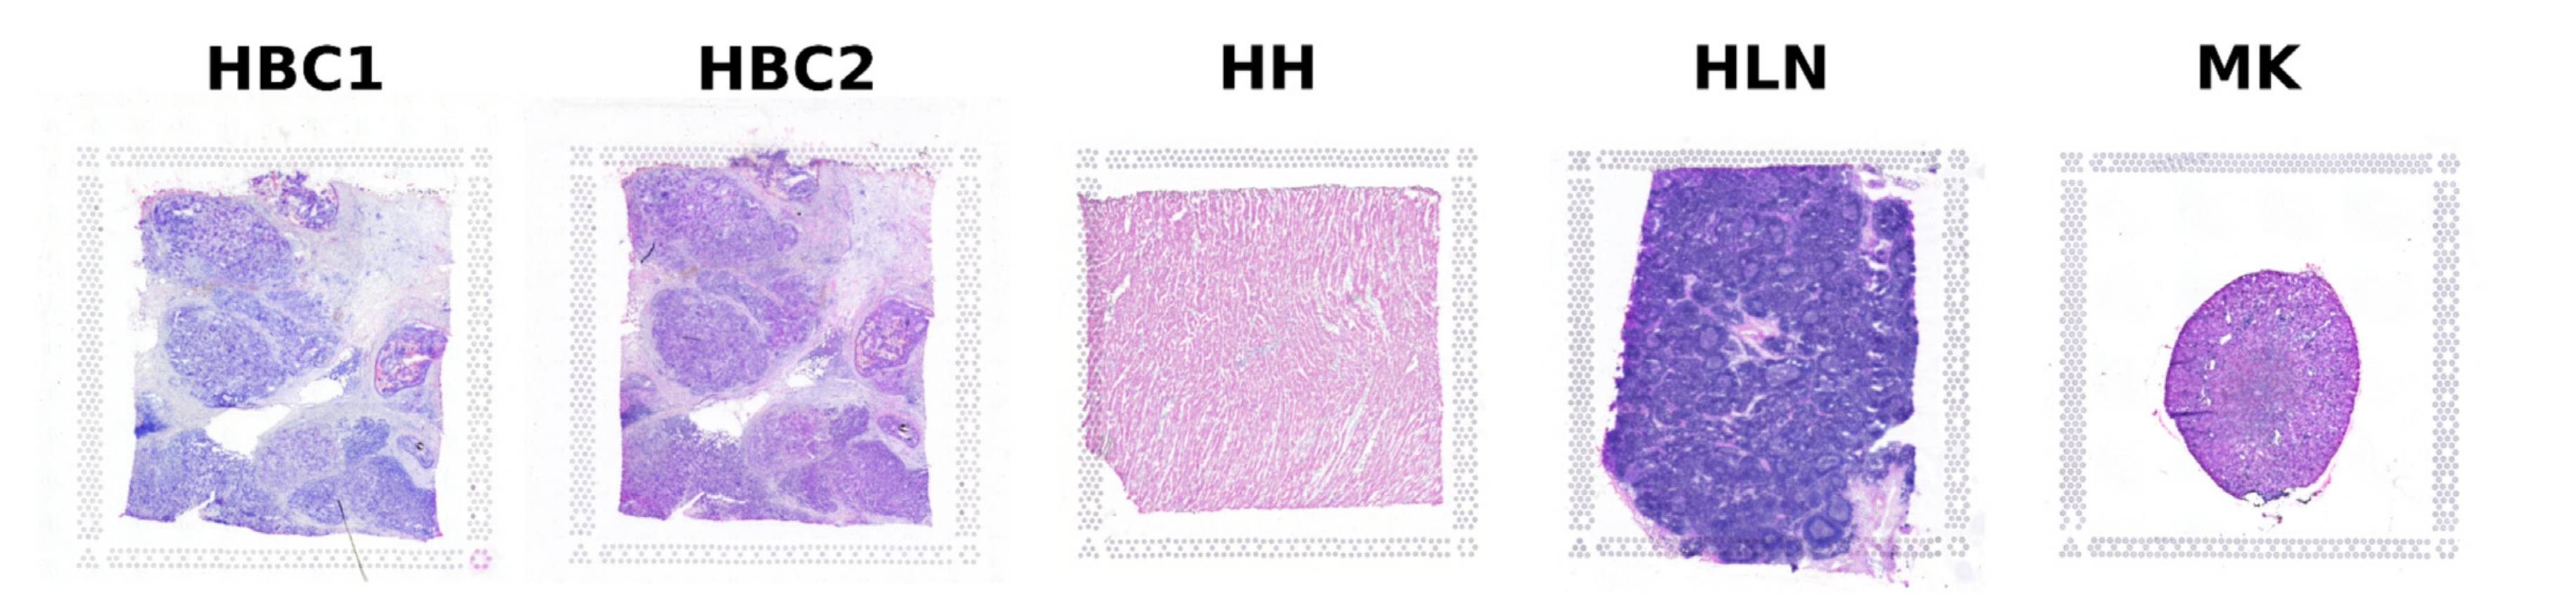

Li X. et al. - 2025

SPEX: A modular end-to-end platform for high-plex tissue spatial omics analysis

Condition Dimension

N/A

Data Components

Gene Expression Matrix

Data

Metadata

None

Modality

Proteomics

Resolution of observation

Cellular

Visualized Elements

FeatureObservation

Biological

Molecular

Abstraction

CompleteNone

Chart Type

Dimensionality reductionScatterplotSpatial Gene Expression Map

Communicative/Contextualization

Annotation

Comparative Design

JuxtapositionJuxtaposition : Small multiples

Layout

Spatial : LatentSpatial : Physical

Scalability Strategy

Sampling/Filtering

Where are specific proteins expressed in both expression space and physical tissue space?